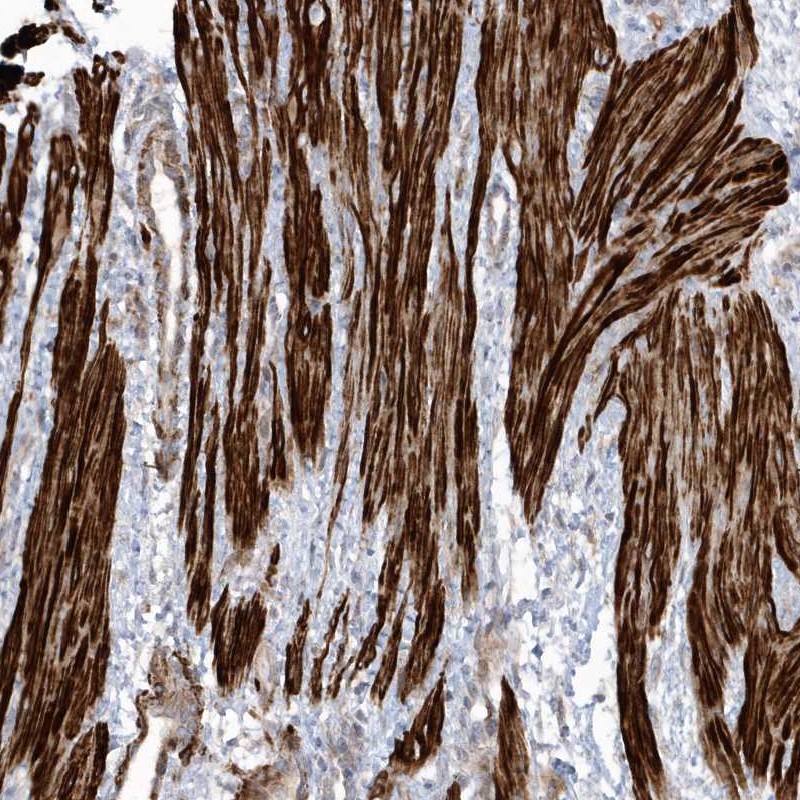

Immunohistochemical staining of human smooth muscle shows strong cytoplasmic positivity in smooth muscle cells.